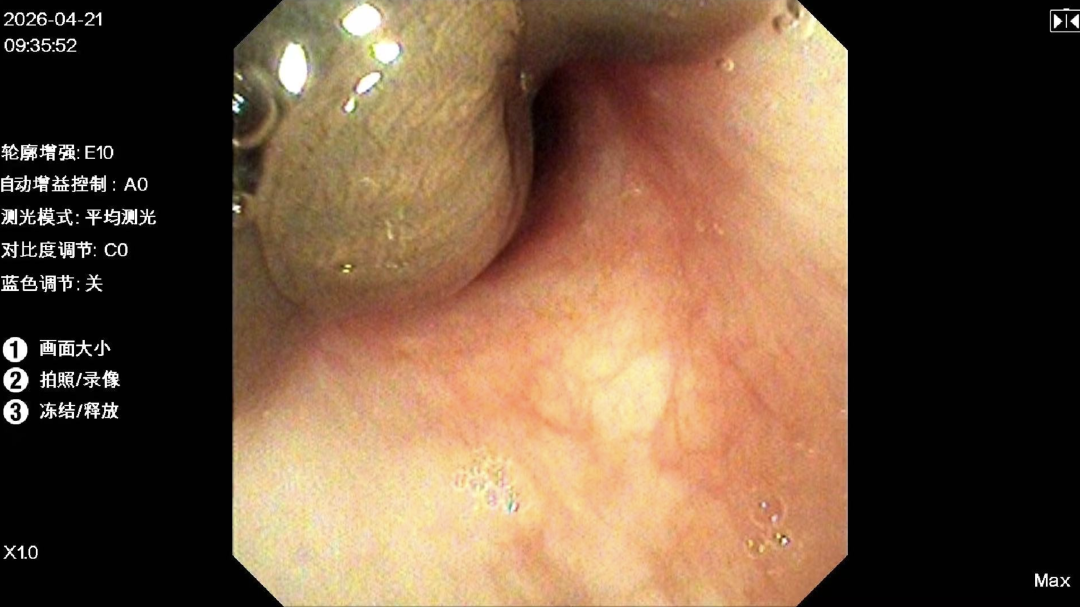

在完善各项检查和谈话后,麻醉科主任医师尹卫国为患儿进行全麻,张学祖医生操作着气管镜,缓缓经鼻腔进入,正要通过声门。

就在这时,一条巨大的活体异物赫然出现在屏幕上方。

图源:治疗团队提供

这条异物堵在声门下、环状软骨附近,紧紧吸附在气管黏膜上,随着患儿的呼吸一上一下蠕动,呼气时几乎堵塞整个气道。

一条活着的蚂蟥!